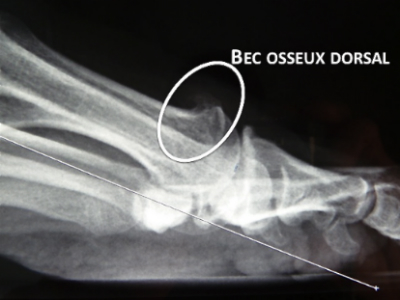

Arthrose du premier orteil ou HALLUX RIGIDUS

L'arthroplastie de Valenti

L’Intervention de Valenti ou arthroplastie des 2 versants articulaires:

Il s’agit de la recoupe de la tête métatarsienne et de la base de la 1e phalange permettant de récupérer de la flexion dorsale sans raccourcissement important.

Les surfaces articulaires sont enlevées par une section en V à 90° en conservant leur paroi plantaire.

Le cartilage plantaire existant en face des sésamoïdes est laissé en place.

Cette conservation plantaire permet de maintenir la longueur globale.